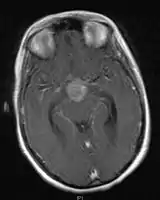

- Mainly located in midline structures, suprasellar region or pineal gland, also basal ganglia and hypothalamus

- Pineal Gland Germinoma

- Suprasellar Germinoma